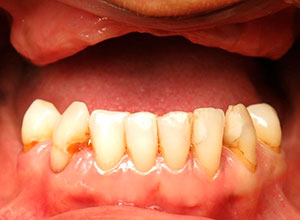

Antes de la Cirugía de Implantes

Después con Prótesis Definitiva fija